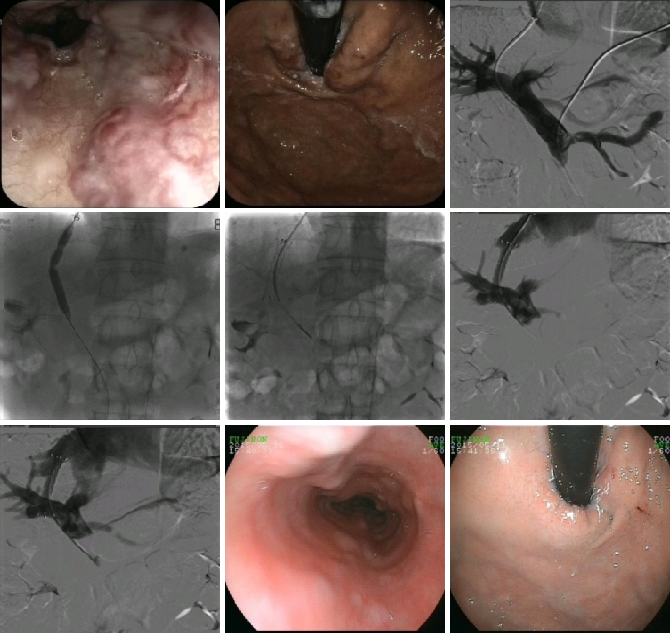

TIPS手术

PTCD胆道支架植入术